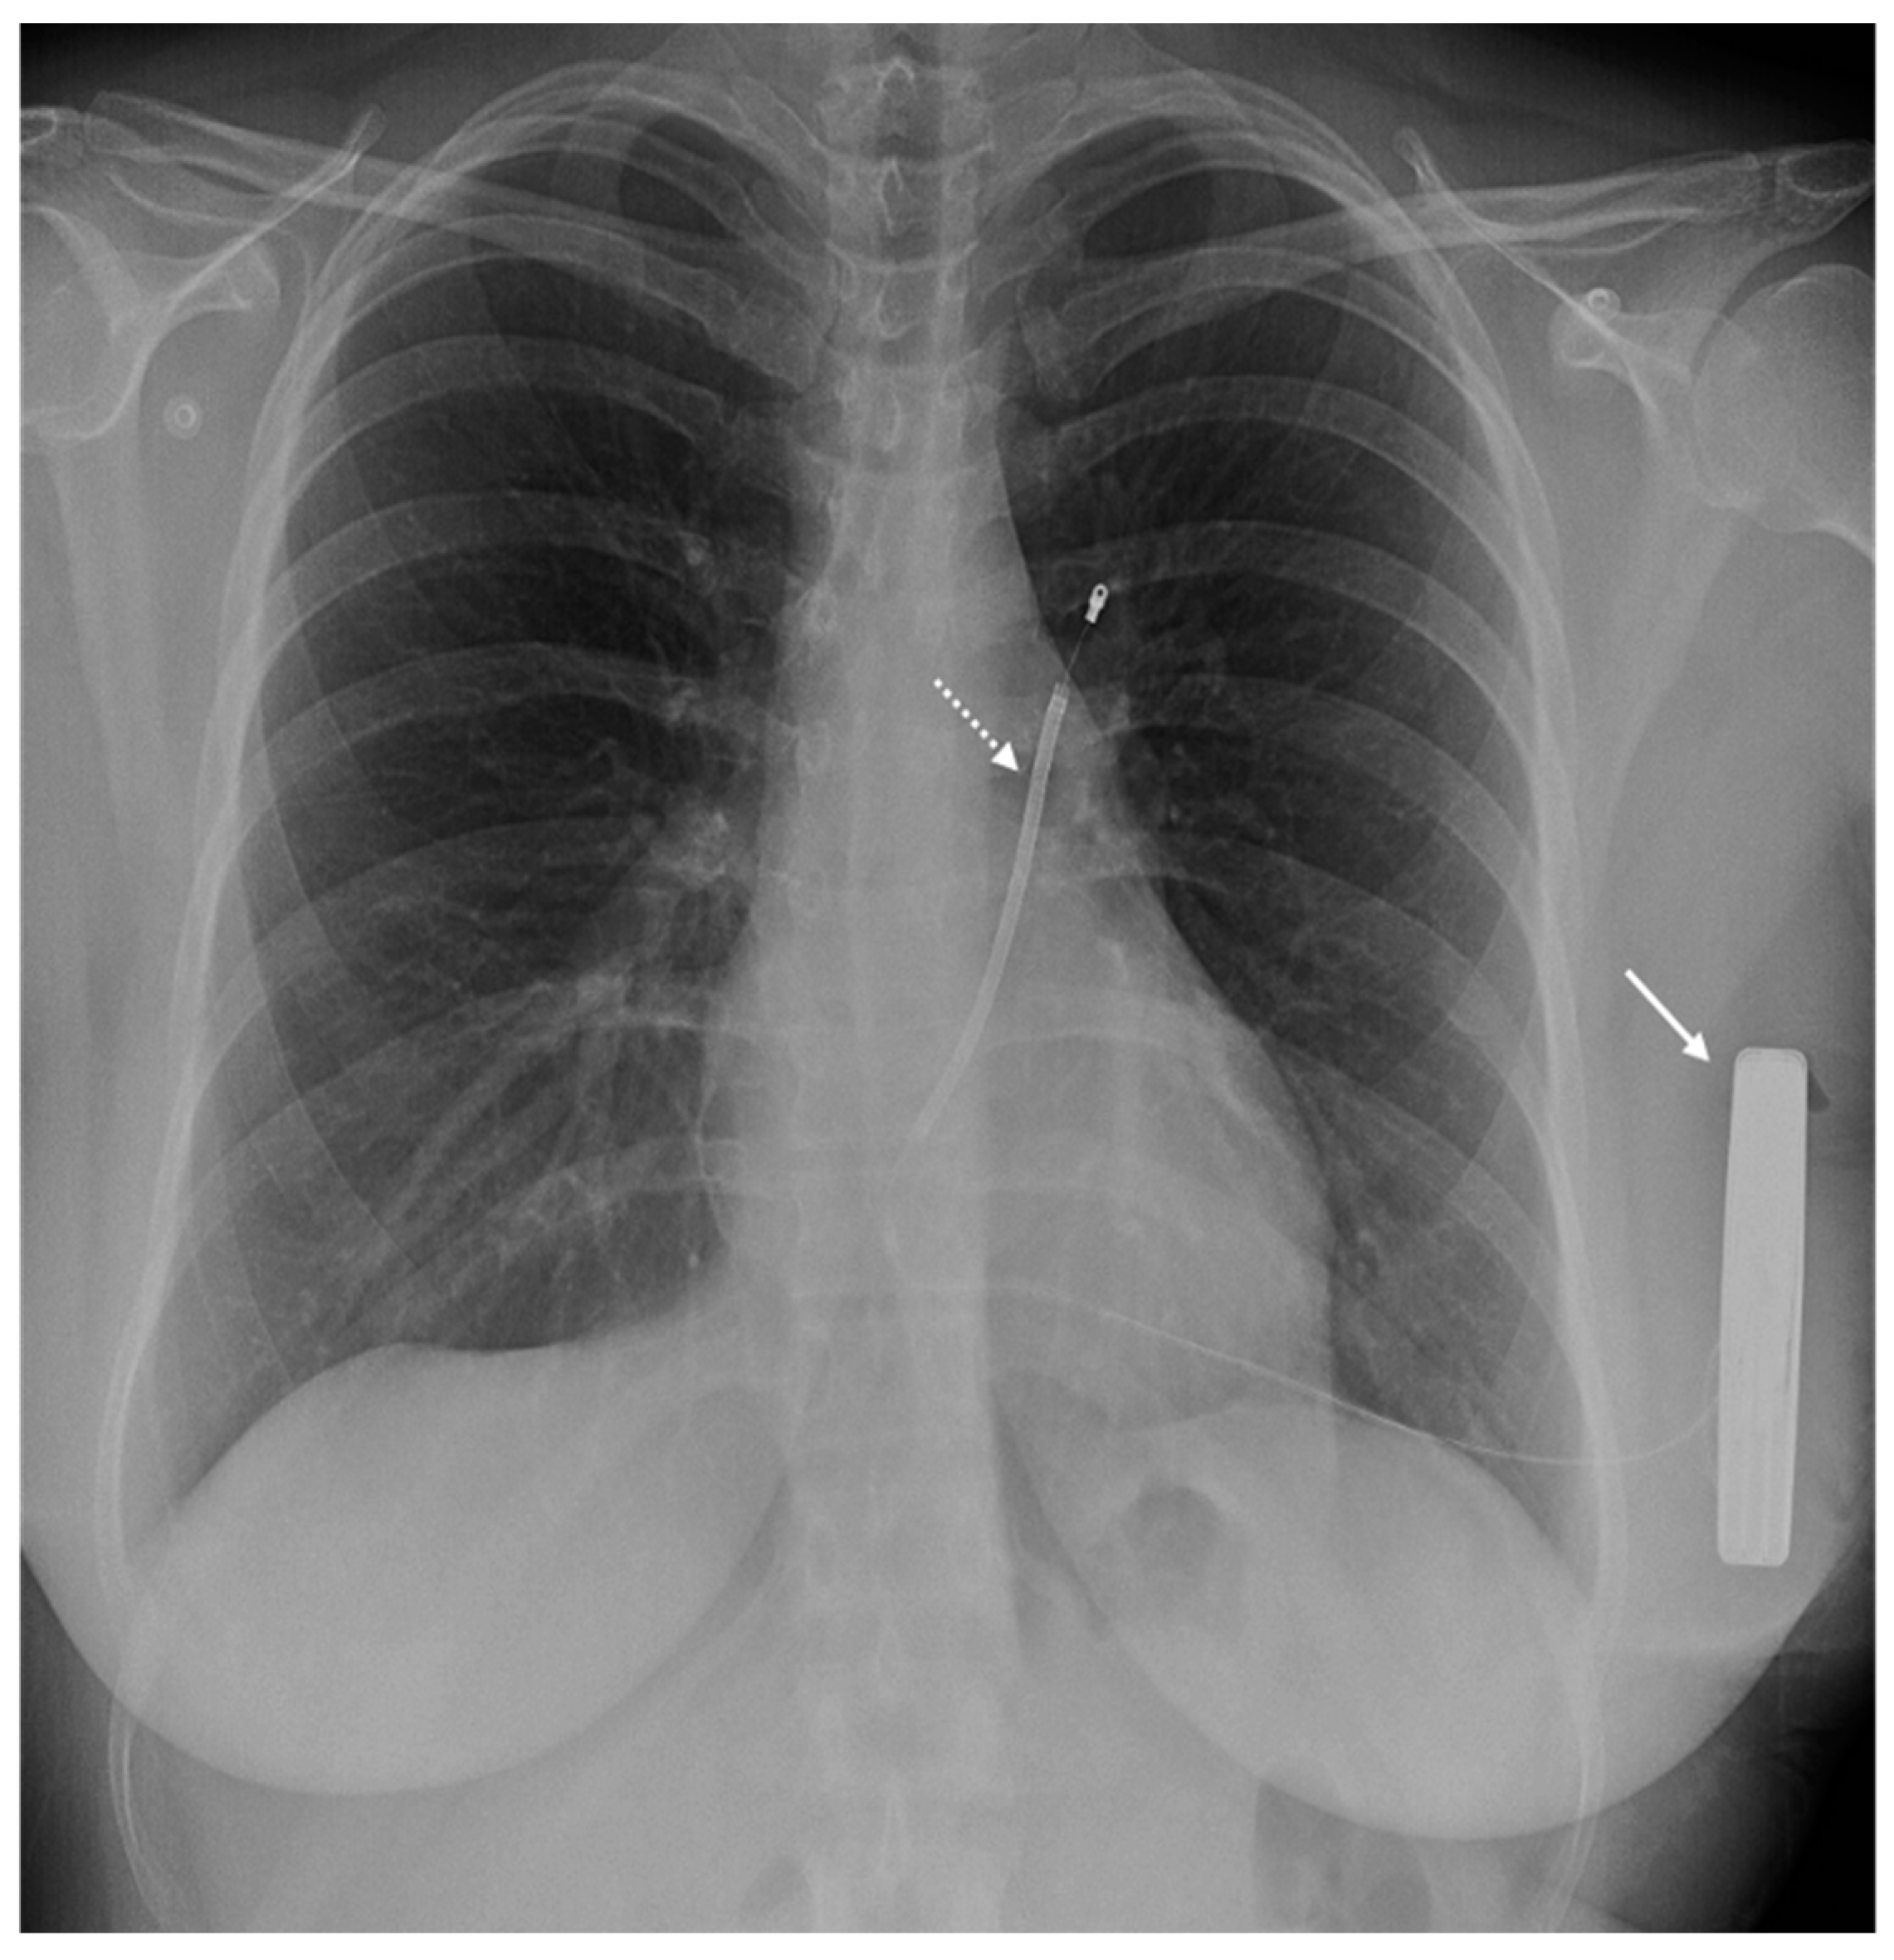

6. Issue: Artifact

- Vuorinen, A.-M.; Lehmonen, L.; Karvonen, J.; Holmström, M.; Kivistö, S.; Kaasalainen, T. Reducing cardiac implantable electronic device–induced artefacts in cardiac magnetic resonance imaging. Eur. Radiol. 2022, 33, 1229–1242. [Google Scholar] [CrossRef] [PubMed]

| Types of Artifacts | Factors that Influence Artifacts | High Artifact | Low Artifact |

|---|---|---|---|

| Signal loss artifact Hyperintensity artifact | CIED’s dimension | Large device | Small device |

| CIED’s position | Left-sided implantation | Right-sided implantation | |

| Magnetic susceptibility | High ferromagnetic component | Low ferromagnetic components | |

| High static MF | Low static MF | ||

| Distance from the region of interest | Proximity to the heart | Elevate the patient’s arm | |

| MRI sequences used | Cine SSFP | SGE sequences | |

| LGE sequence with a bandwidth of about 1 kHz | LGE sequence with a wide bandwidth |